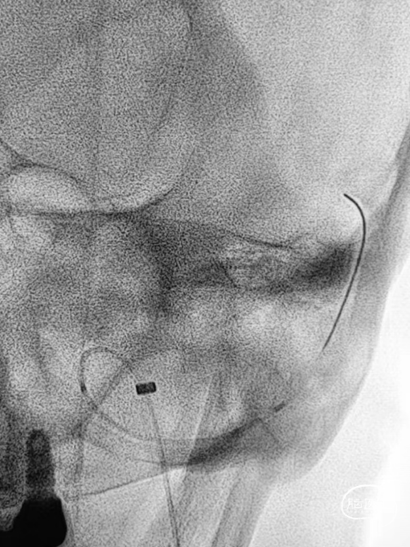

➤DSA

路图下,沿Command 18导丝将8×40mm Xpert Pro支架输送至乙状窦,使用支架近远端marker点进行准确定位,整个推送过程顺利,无明显阻力。

随即释放Xpert Pro支架以覆盖憩室开口,支架打开后显影清晰,贴壁良好。使用微导管穿出支架网孔,并置入憩室内进行弹簧圈填塞。单微导管填塞过程弹簧圈成篮较为困难。

使用双导管继续在Xpert Pro支架辅助下进行弹簧圈填塞,再次造影显示:憩室内血液已完全阻滞,未见显影。

Xpert Pro支架在乙状窦内形态良好。静脉窦憩室闭塞完全。